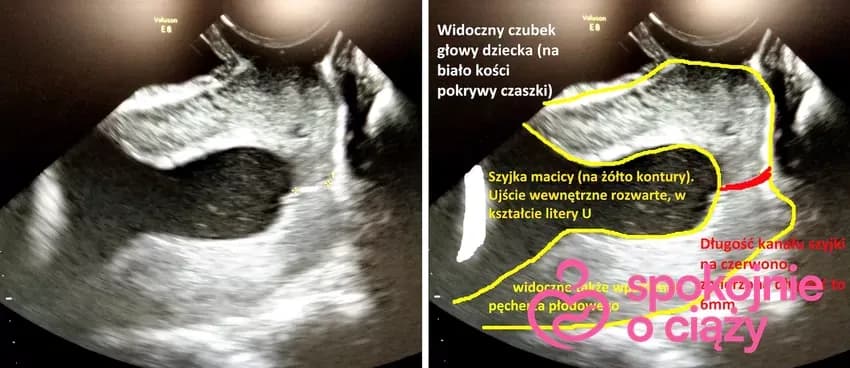

Dowiedz się, jak skrócona szyjka macicy wpływa na termin porodu. Poznaj objawy, metody monitorowania i możliwe interwencje medyczne. Ważne informacje dla przyszłych mam.